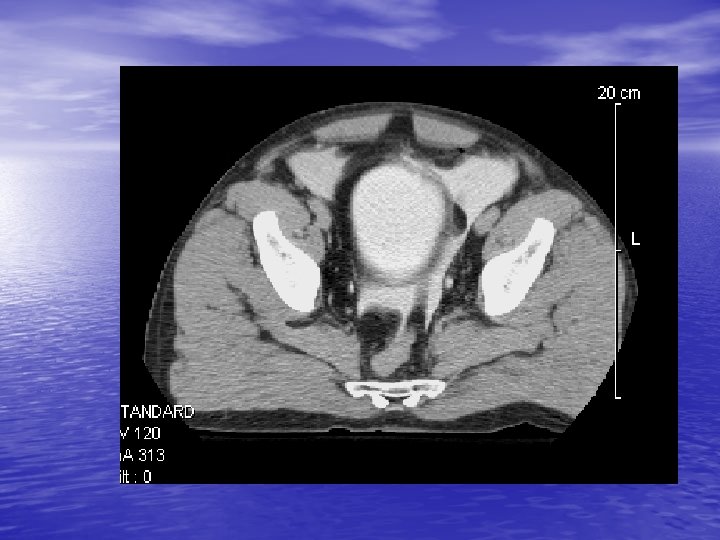

Bladder Injuries • Less than 2% of all abdominal injuries • 6 -10% of pelvic Fx----Bladder rupture • 10 -14% of pelvic Fx---- Urethral rupture • 83 -100% of bladder rupture---- Pelvic Fx • 10 -29% of bladder rupture---- Urethral rupture • 2% of the urethral ruptures is in female

Bladder Rupture • More hematuria---- More injury • Any Degree of hematuria and lower abdominal injury • • needs evaluation Dx: Cystography (20%) & CT-Cystography(2 -4%) Management: All intraperitoneal ruptures except? Extraperitoneal when? -Bone Fragment -Open pelvic Fx -Rectal perforation -Clot obstruction -Laparotomy for other reason

Mechanism of Bladder Injuries (extraperitoneal)

Extraperitoneal Rupture

Distension of the Urinary Bladder

Intraperitoneal Rupture